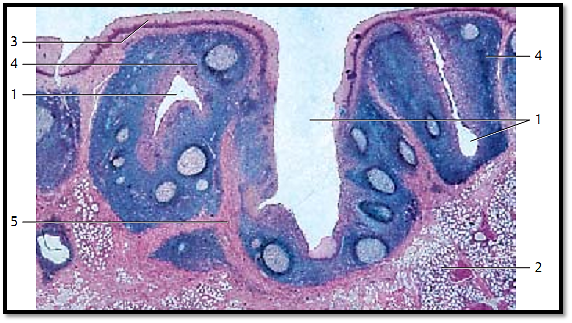

Lingual Tonsil

The root of the tongue between sulcus terminalis and epiglottis features tonsillar crypts 1 . These are short narrow caverns (invaginations). The tonsillar crypts may continue in the secretory ducts of mucous glands 2 or have a blind end. The crypts are lined by multilayered nonkeratinizing squamous epithelium and surrounded by lymphatic tissue. The figure shows the multilayered squamous epithelium 3 , which covers the root of the tongue and its crypts (invaginations, caverns) 1 . The lymphoreticular tissue (stained deep blue) 4 underneath the epithelium is part of the lamina propria. Numerous more lightly stained areas are found in the lymphoreticular tissue. These are secondary follicles. The lymphoreticular tissue is separate d from the surrounding tissue by a more or less complete connective tissue capsule 5 .

1 Tonsillar crypts

2 Mucous glands of the root of the tongue, glandulae linguales posteriores

3 Epithelium of the lingual mucous membrane

4 Lymphoreticular tissue with germinal center s

5 Connective tissue capsule

Stain: alum hematoxylin-eosin; magnification: × 14